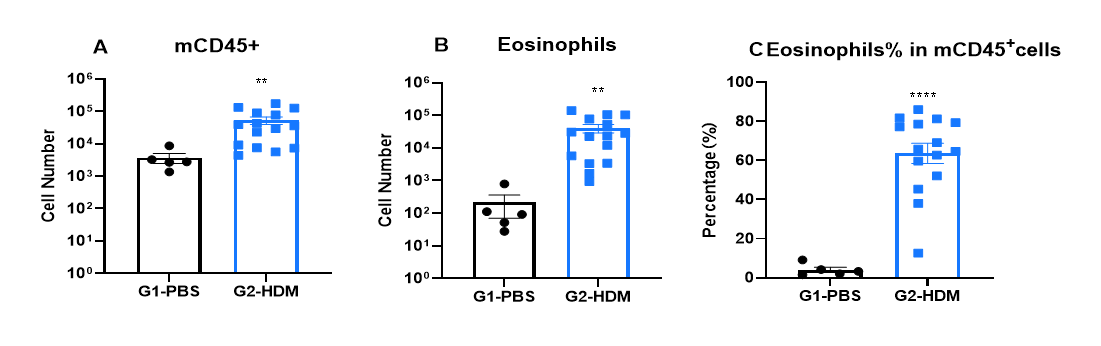

Immune Cell Infiltration in Bronchoalveolar Lavage Fluid (BALF) of Asthmatic Mice

Increased Immune Cell number in BALF of OVA-induced mice compared with controls. BALF was collected at the end of the experiment and CD45+ cells number (A), eosinophils number (B) and the percent of eosinophils in CD45+ cells (C) were measured by flow cytometry.

Increased IgE levels in serum of HDM-induced mice compared with controls. Serum was isolated at the end of the experiment and concentrations of total IgE were measured using ELISA.

H&E staining of lung tissue in HDM-induced asthmatic C57BL/6 mice. Compared to G1 controls, G2 mice treated with house dust mite (HDM) exhibited characteristic asthma pathology, including vascular and peribronchial inflammatory cell infiltration (b) and mucus production (a). These findings confirm that HDM successfully induces asthma in wild-type C57BL/6 mice.